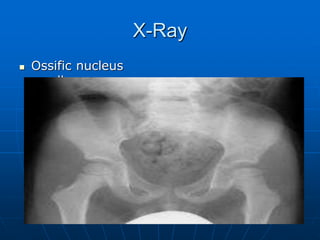

X-Ray

 Ossific nucleus

smaller